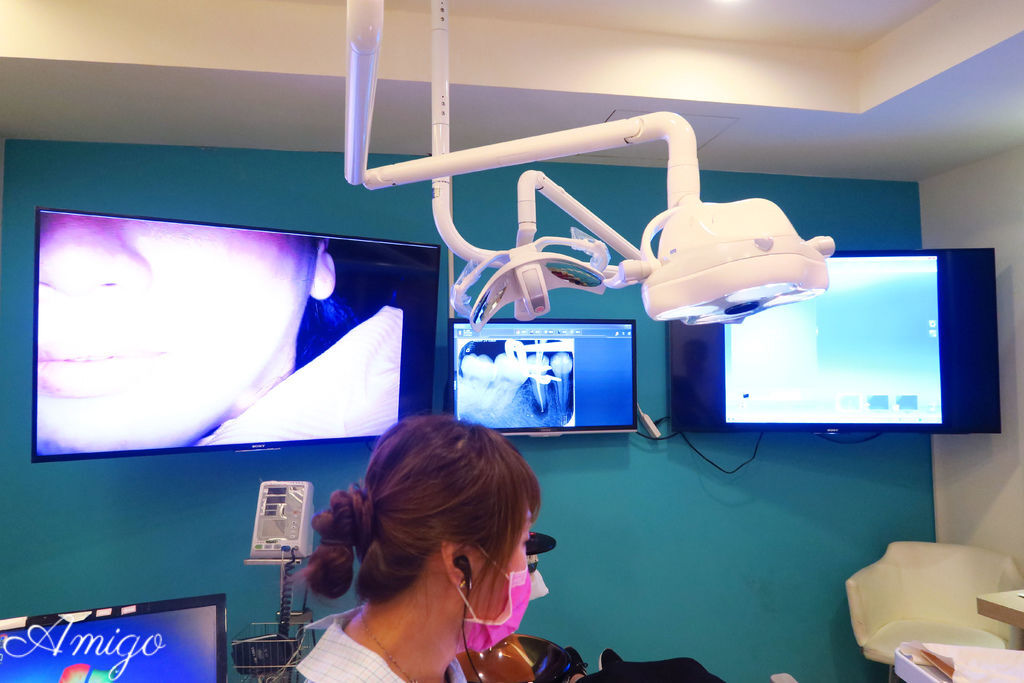

接下來就進入診間看看醫師看診的情況吧~

明亮的診間裡

透過大螢幕來觀看患者口內狀況以及3D影象投射

整個治療過程都在螢幕上清楚呈現

當天的case是一位做全瓷冠假牙的患者

做案例說明的是院長曹醫師

曹醫師年輕又專業

早年曾到過美國學習 之後才帶領著牙醫及技師們開設悅庭牙醫診所 隨後設立數位全瓷研磨中心

優秀的他能夠早早洞悉並帶動台灣牙醫的趨勢真的很不簡單~

本次病患做假牙的部位是畫面左邊倒數第三顆的小臼齒

曹醫師先將真牙磨成適合放置牙套的大小